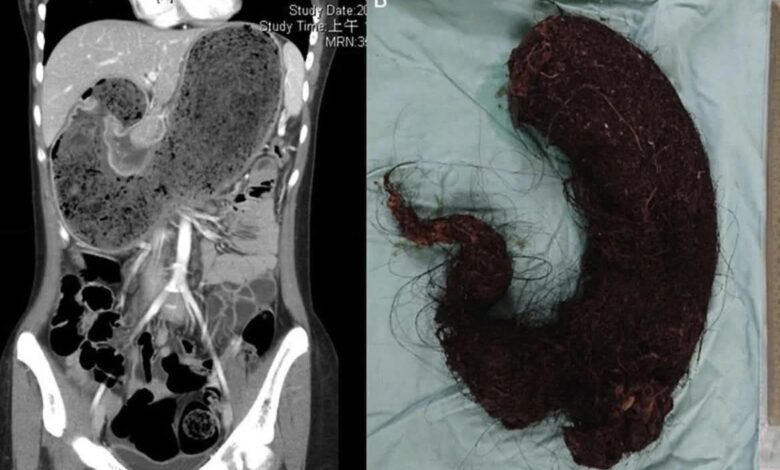

في ظاهرة طبية مدهشة، رصد الأطباء حالة نادرة تسمى متلازمة رابونزيل، التي تكشف عن مدى تعقيد اضطرابات السلوك البشري وتأثيرها على الجسم، المرضى هنا لا يكتفون بنتف شعرهم فحسب، بل يبتلعونه باستمرار، ما يؤدي إلى تراكمه في المعدة وتكوين كتلة صلبة ضخمة تشبه شكل الجهاز الهضمي الداخلي.

الكتلة الناتجة عن تراكم الشعر تسمى Trichobezoar في متلازمة رابونزيل، هذه الكتلة لا تبقى في المعدة فقط، بل تمتد إلى الأمعاء الدقيقة، وقد تصل أحيانًا للقولون. حجمها أحيانًا يصل إلى كيلوغرامات، وشكلها يكرر شكل المعدة والأمعاء، ما يجعلها حالة خطيرة تستدعي التدخل الطبي الفوري.